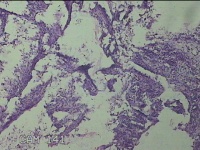

子宫肌瘤结节

性别

女

年龄

35岁

临床诊断

多发性子宫肌瘤 继发性不孕症 子宫Ⅰ度脱垂 高脂血症 胆囊息肉

一般病史

发现子宫肌瘤4年余,继发不孕3年。

标本名称

大体所见

灰白暗红色圆形肿物10x9x2.8㎝九个,表面糜烂,切面均为灰白色结节状或编织状,质中。

良性病变。

考虑平滑肌瘤。